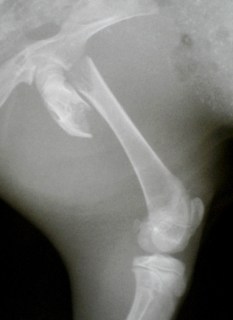

Σπειροειδές κάταγμα εγγύς μετάφυσης μηριαίου οστού σε κουνέλι 4 μηνών. |